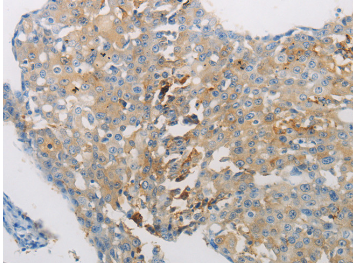

| Immunohistochemistry of Human brain using AATK Polyclonal Antibody at dilution of 1:10 |